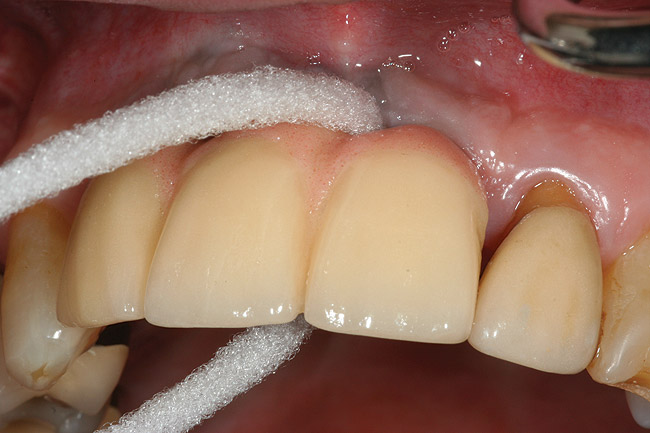

Locally delivered, controlled-release agents are a popular treatment adjunct and serve to augment scaling and root planing to help improve outcomes. Clinical studies have shown that use of such agents can provide an average of 0.5-mm additional pocket depth reduction over scaling and root planing alone, so the practitioner must weigh the cost-benefit ratio of using these products in each patient situation.39,40 A guideline for the appropriate use of locally delivered antimicrobials has been provided by the American Academy of Periodontology.41 These materials are contraindicated in patients with (1) multiple 5-mm pocket depths in one quadrant; (2) anatomic defects caused by periodontal diseases (intrabony defects); and (3) when the previous use of locally delivered agents has failed to control disease. As noted before, a follow-up reevaluation always should be completed to evaluate the success of any therapeutic intervention, generally at 4 to 6 weeks after treatment has been rendered30,31 (Figure 3A through Figure 3D).

Figure 3c  The site was treated by localized scaling and root planing, followed by use of Arestin (minocycline microspheres).

Figure 3c

Figure 3d  The resolution of inflammation and bleeding on probing on the reevaluation appointment 6 weeks later.

Figure 3d